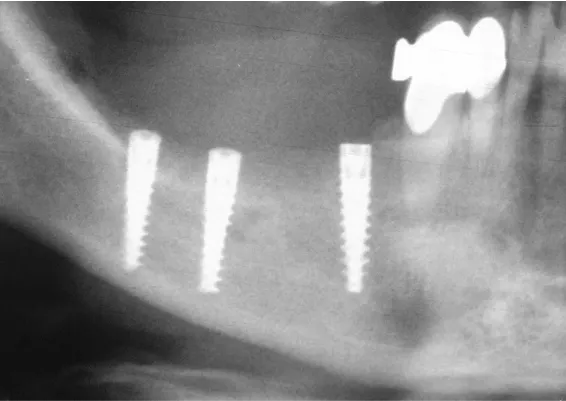

ZABIEGI REGENERACJI KOSTNEJ WOKÓŁ WSZCZEPIANYCH IMPLANTÓW

Sterowana regeneracja kości GBR przy użyciu biomateriałów oraz membran zaporowych. Procedury te są stosowane w sytuacji niedostatecznej ilości kości, skutkującej odsłonięciem gwintu, podczas gdy wszczepiamy implanty stomatolo-giczne lub też jako zabiegi poprzedzające ich wprowadzenie.

Metoda rekonstrukcji kostnej w oparciu o indywidualnie drukowane siatki z tytanu dla implantacji wszczepów śródkostnych stosowana jest najczęściej jako dwuetapowa. W pierwszym etapie odbudowywana jest kość, natomiast implanty wszczepiane są po okresie 4–6 miesięcy. Na wgojenie implantów oczekujemy od 4 do 6 miesięcy w zależności od miejsca ich lokalizacji. Siatka tytanowa po spełnieniu swojej funkcji rusztowania dla odbudowującej się kości jest następnie usuwana w dniu wszczepienia implantu. Jeżeli kość spełnia odpowiednie warunki, istnieje możliwość zastosowania modyfikacji siatki tytanowej, która umożliwia jednoczesne wprowadzenie implantów wraz z odbudową kostną.

Wariant ten skraca czas od pierwszego zabiegu do wykonania gotowych koron protetycznych na wprowadzonych implantach. Opisane schematy procedur regeneracyjnych wykazują znaczną innowacyjność, jeśli chodzi o wykorzystanie technologii cyfrowej w medycynie odtwórczej. Natomiast w codziennej praktyce chirurgicznej poprawiają precyzję, tempo oraz przewidywalność w świadczeniu usług polegających na odbudowie zniszczonych lub zdeformowanych ludzkich tkanek.